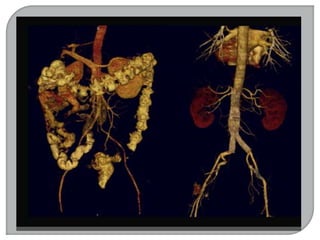

-TOMOGRAFIA COMPUTADORIZADA

 Em 1967, iniciaram-se as 11 pesquisas sobre

reconhecimento de imagens e técnicas de

armazenamento de dados em um computador.

 Em 1971 foi realizado o primeiro teste de um

“SCANNER” do crânio, num hospital de Londres.

 O scanner foi apresentado oficialmente em 1972.

 A.M Comark (Físico norte americano) e Geoffrey

Hounsfield (engenheiro inglês).

 EMI primeira empresa a fabricar o scanner.

Gravadora de discos (Beatles).

 Reconhecidos como TOMÓGRAFOS

COMPUTADORIZADOS.

 Em 1979, estes dois cientistas receberam o

prêmio Nobel.